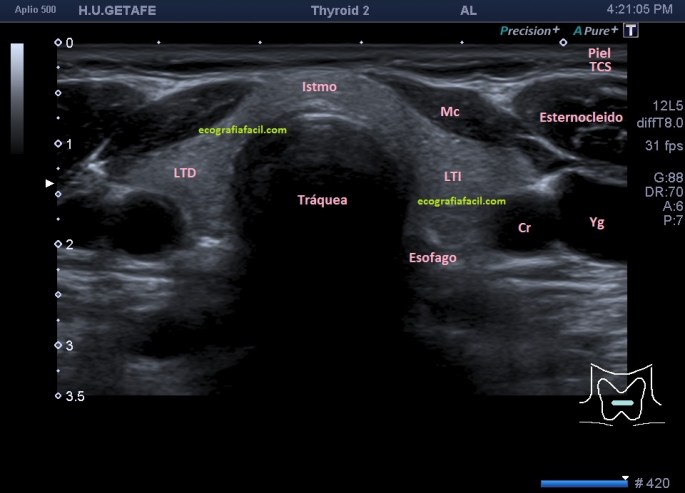

En el protocolo de Tiroides debemos estudiar ambos lóbulos, istmo y ganglios locorregionales como objetivo primordial. No menos importante, otras ecoestructuras como vasos, glándulas salivares, musculatura anterior, tráquea, esófago, cartílagos, es decir, no nos quedamos en una mera exploración de la glándula tiroidea, sería un error, perderíamos patologías importantes extratiroideas como te demostraré en un próximo post sobre el tiroides en el que estoy trabajando.

En la exploración objetivamos una glándula tiroidea aumentada de tamaño, sin imágenes nodulares, pero si heterógenea toda ella con afectación global en ambos lóbulos tiroideos. Semiológicamente se observa una y/o hiperplasia glandular y es muy significativo un abombamiento anterior de la glándula, con unas medidas elevadas discretamente respecto de sus medidas en rango de normalidad, es decir, la paciente tiene bocio no nodular y además alteración en la ecogenicidad de la glándula, pero lo más llamativo fue cuando puse el doppler para estudiar la vascularización de ambos lóbulos tiroideos. Era una vascularización elevada, mucho más que la normal vascularización de esta glándula. Es el conocido Infierno Tiroideo.

Lo primero, reconoce siempre la normalidad para poder identificar anormalidad. En la imagen 1 tienes una imagen normal de ambos lóbulos tioideos en un corte axial (nos sirve para repasar anatomía básica), en la imagen 2 un corte longitudinal de uno de los lóbulos con su vascularización típica. Bien guarda en tu cabecita estas dos imágenes y ponte en modo concentración para descubrir los cambios semiológicos en el caso de la paciente referida con anterioridad.